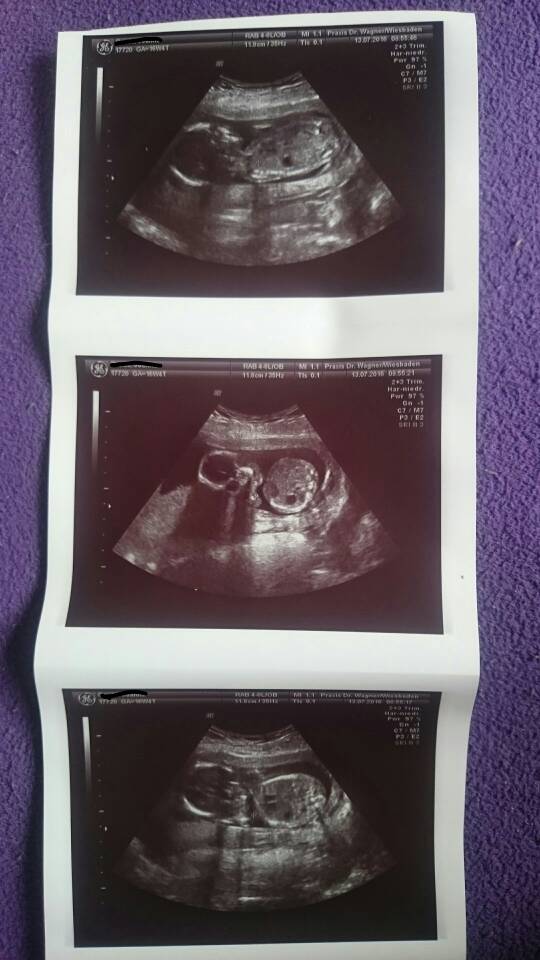

Zobacz załącznik 762887Zobacz załącznik 762888Zobacz załącznik 762889Zobacz załącznik 762890

No lekarz dziewczyny naprawdę taki ludzki jest. Świetny gościu. Zapomniał mi fotkę wydrukować [emoji6], i już ubrana mówię, od szkoda ze nie dostałam fotki maluszka, a on o faktycznie! To się rozbierać jeszcze raz zrobimy usg , żaden problem żeby druknac. [emoji7]

No który lekarz dziewczyny zrobił by usg jeszcze raz żeby tylko dla mojego widzimisię fotkę mi zrobić [emoji7]. Dlatego zaczęłam go bardzo szanować, widać że traktuje pacjentki każda indywidualnie a nie Leci taśmowo hurtem jak niektórzy.